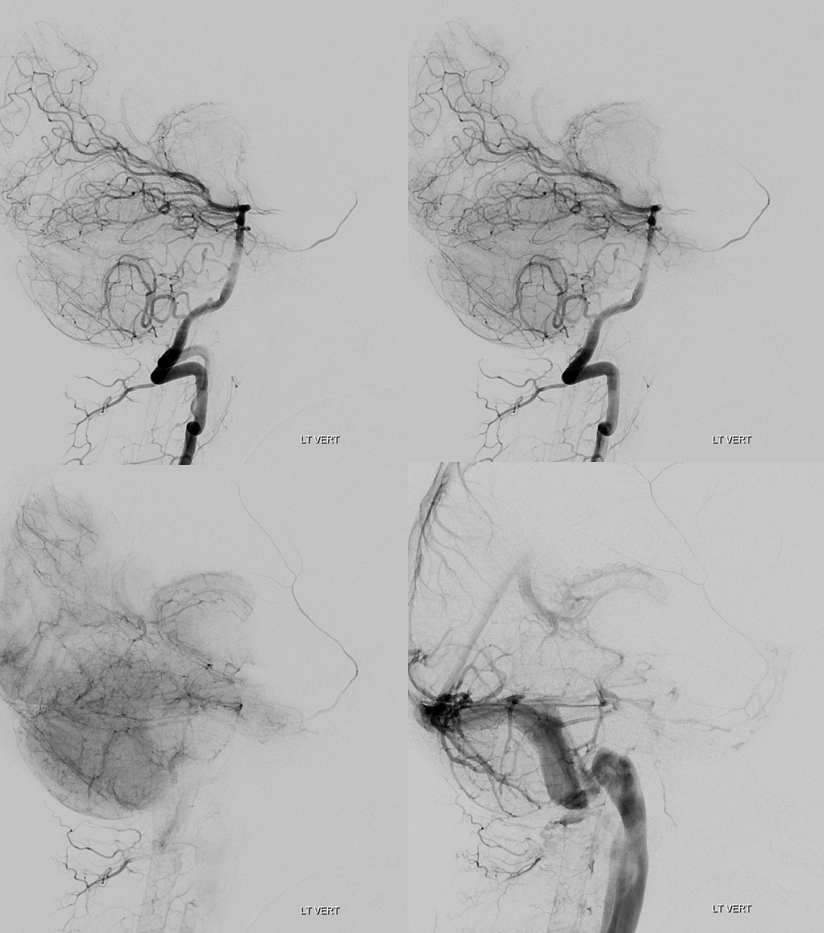

Trigeminal Supply of Superior Cerebellar, AICA, and lateral / hemispheric PICA

Neat. And extremely rare — i am not sure there is another example out there. I am very sure however that there are many people like that walking around, with no problems at all.

I guess that would be Saltzman IIIA+IIIB+IIIC/2. This is either very advanced algebra or a reflection on classifications in general — you decide. The important thing is to put everything together and understand what goes where

Angio shows large trigeminal with clear supply of the SCA on lateral view. Vert injection shows no right SCA. There is a diminuitive branch from mid-basilar projecting laterally — that is likely the right labyrinthine artery — what is embryologically solid AICA territory. The rest is taken by the trigeminal. The right PICA is limited to vermian territory. The inferolateral hemisphere is supplied by the trigeminal as well. Dont look for arrows. You should figure it out.

DYNA VR. White arrow — vermian branch SCA; dashed white arrows — lateral hemispheric branches of SCA; red arrow — AICA. Note inferior extension towards PICA territory.

Stereos

Movie VR

MIP images. Superior vermian territory = white oval; lateral SCA territory = dashed white oval; AICA (minus the labyrinthine branch) = dashed black oval; inferior PICA/down to tonsillar branch = black oval

Movie MIP